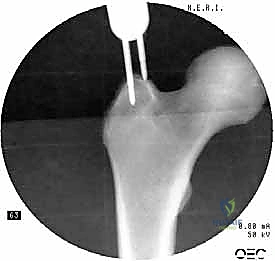

2. الرد المغلق (Closed Reduction)

باستخدام جهاز الأشعة السينية المرئية المستمرة (C-Arm Fluoroscopy) داخل غرفة العمليات، يقوم الدكتور هطيف بإعادة العظام المكسورة إلى محاذاتها التشريحية الصحيحة عن طريق الشد والتدوير الخارجي للساق، وكل ذلك يتم مراقبته على الشاشة بدقة متناهية.

4. توسيع القناة وإدخال المسمار

يتم استخدام أدوات حفر خاصة (Reamers) لتوسيع القناة النخاعية بلطف لتستوعب المسمار المصنوع من التيتانيوم. بعد ذلك، يتم انزلاق المسمار النخاعي الرئيسي داخل العظم حتى يصل إلى العمق المطلوب.

5. تثبيت عنق ورأس الفخذ (المسمار الرأسي)

من خلال ذراع توجيه متصلة بالمسمار الرئيسي، يتم إحداث ثقب في عنق ورأس عظمة الفخذ. يتم إدخال المسمار الرأسي (Cephalic Screw) السميك ليمسك برأس الفخذ بقوة ويسحبه نحو المسمار الرئيسي، مما يضغط الكسر (Compression) ويحفز التئام العظام بسرعة.